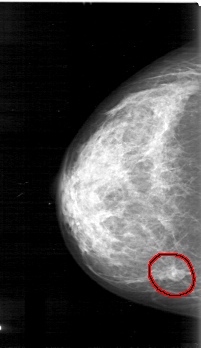

D_4031_1.RIGHT_CC

FILE: D_4031_1.RIGHT_CC.OVERLAY

TOTAL_ABNORMALITIES 1

ABNORMALITY 1

LESION_TYPE MASS SHAPE OVAL MARGINS OBSCURED

ASSESSMENT 0

SUBTLETY 5

PATHOLOGY BENIGN

TOTAL_OUTLINES 1

BOUNDARY